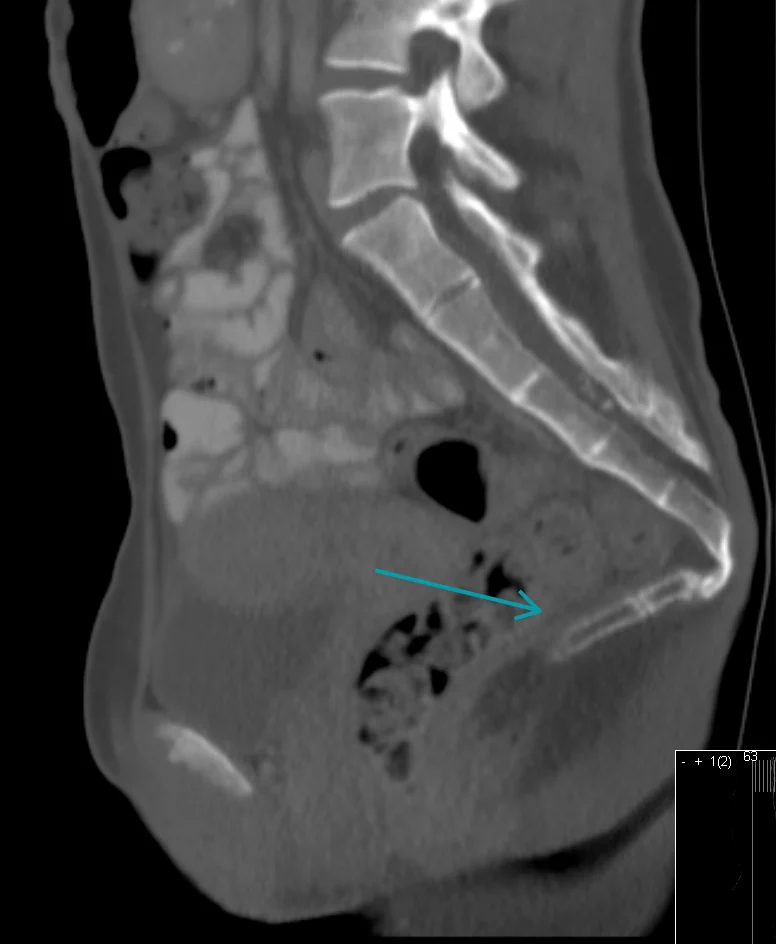

Od slikovnih pretraga najčešće se koriste:

- CT (kompjutorizirana tomografija) – prikazuje detaljnije koštane strukture i može otkriti tumore.

Ipak, kod mnogih pacijenata standardne slikovne metode, poput RTG-a, CT-a i MR-a, ne otkrivaju jasne abnormalnosti. Zato je za postavljanje dijagnoze često presudan temeljit klinički pregled i dobra anamneza, uz isključivanje drugih mogućih izvora boli u donjem dijelu kralježnice.